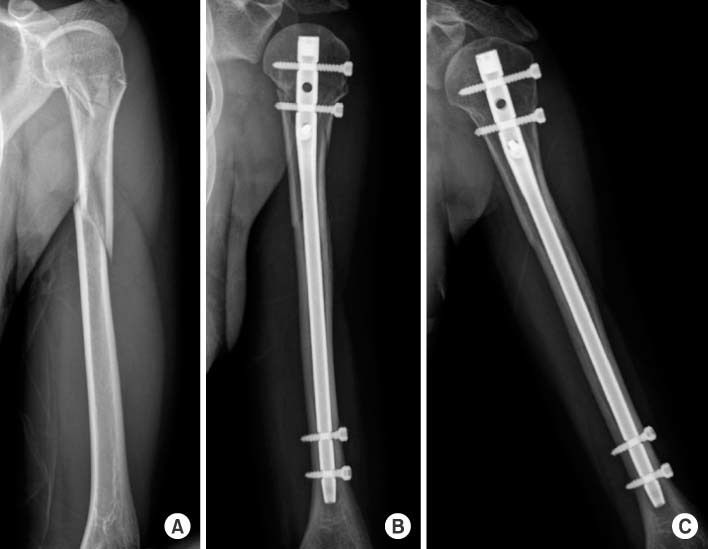

INTRAMEDULLARY NAILING anterograde/retrograde** indicated in patho, segmental and osteoporotic fractures COMPRESSION PLATING method of choice for fixing fractures better union rate and lower complication rate compared with nailing COMPLICATIONS OF SURGERY (definite): infection, delayed/non union, nerve damage (radial nerve palsy) most humeral fractures treated conservatively radial nerve involvement should be checked 90% heal well